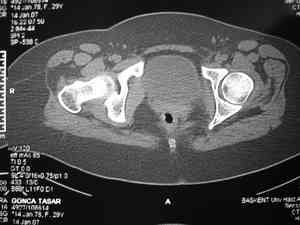

Dear group,30 years age female MVA front seat, head trauma + post column left acetabular fracture, 2.5 weeks skeletal traction. She is now conscious but still confused without any surgical treatment for brain edema.

Latest X rays and CAT is attached.Fracture within first 1.5 cm from the weight bearing dome, although AP and Obtrator oblique good, iliac oblique view reveals some displacement.I'm not sure that nonsurgical treatment will be OKHüseyin DemirorsBaskent UniversityDept of Orthopedics and TravmatologyAnkara TURKEY

My vote, given the amount of displacement on the iliac oblique and CT scan, would be for ORIF thru a posterior approach ASAP - these get pretty tough

CT scan taken 5 days ago and radiographs taken today

I may get beat up for this, but I see very little displacement that concerns me on the CT. The radiograph is more concerning. I suspect it could look better, and the gap made smaller on CT. Not sure if it will affect outcome. I might give it a shot and try to see what could be done.